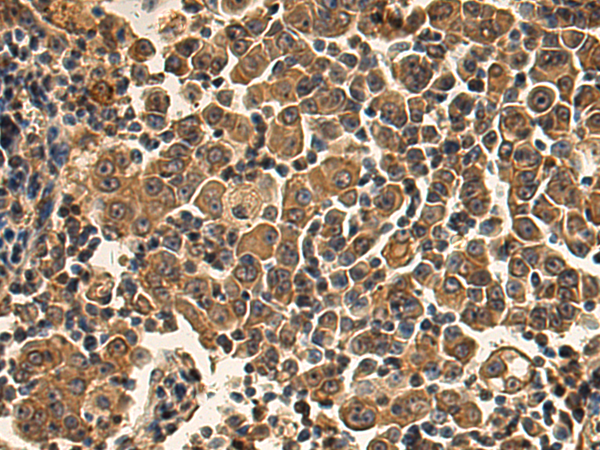

分类: 科研抗体货号: P01859别名: slp5应用: IHC反应种属: Human, Mouse, Rat